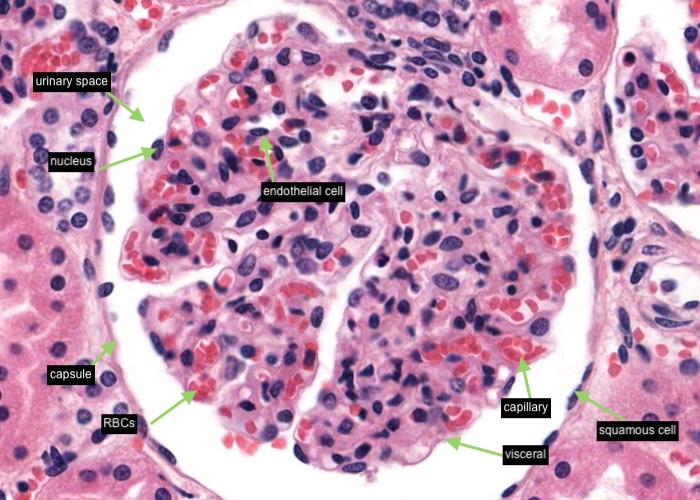

A renal corpuscle is located in the cortex and is the specialised structure where filtration occurs. Each is an aggregation of capillaries enclosed within a cup-shaped capsule called the glomerular (Bowman’s) capsule. Identify red blood cells within these capillaries. The capsule has an outer (parietal) surface layer of squamous epithelial cells and the inner (visceral) layer invests the glomerular capillaries.

The space between the glomerular capillaries and the parietal layer of Bowman’s capsule is referred to as the capsular or urinary space. This space receives plasma fluid that filters through the glomerular capillaries and the visceral layer of epithelial cells called podocytes.

In this H&E section, podocytes are difficult to distinguish from other populations of cells present (e.g. mesangial cells) but assume if you identify a cell nucleus on the periphery of the glomerulus that is larger and more spherical then it is probably a podocyte rather than a flattened nucleus belonging to an endothelial cell. You will see this distinction better when you view the renal corpscule where the basement membrane has been specifically stained and podocytes are definitely outside surface of the basement membrane of the capillary wall.

Interlobular arteries give off tiny afferent arterioles which run into the lobule to supply each renal corpuscle. An afferent arteriole enters a renal corpuscle, breaks up into a tuft of capillaries called a glomerulus, and then collects back into an efferent arteriole instead of a vein. This occurs at the "vascular pole". This is a nice image because it also shows part of a glomerulus with the urinary (tubular) pole visible (see more details in the next item). You may see an arteriole, but it will be impossible to tell whether it is afferent or efferent (although there is a slight hint that it is an afferent arteriole because it is adjacent to a distal convoluted tubule - ignore this though for now!). The efferent arteriole runs for only a short distance before breaking up into a second bed of peritubular capillaries, which nourish the proximal and distal tubules and absorb fluid. Even when these capillaries are collapsed you can easily see abundant red blood cells within their lumens between the convoluted tubules.

Besides the vascular pole (where the afferent and efferent arteriole enters or leaves the glomerulus; see previous item) each renal corpuscle has a urinary (tubular pole) where the proximal convoluted tubule originates. Note that the simple squamous epithelium of the parietal layer of the glomerulus (Bowman's) capsule abruptly changes to a simple cuboidal epithelium in the proximal convoluted tubule.